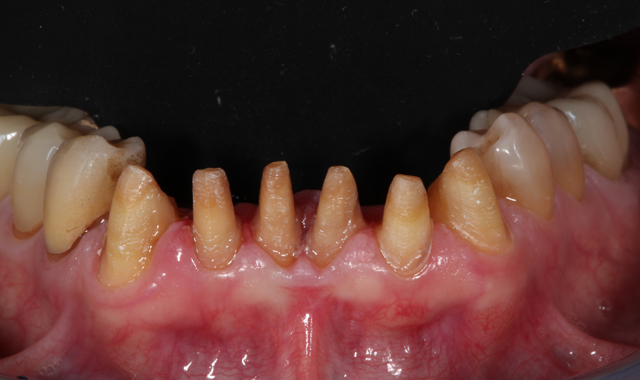

Fig. 1

A male patient in his mid-60s presented with a chief complaint about the esthetics of his anterior maxillary and mandibular teeth (crowding, severe tetracycline staining) (Figs. 1 and 2). Orthodontic treatment was suggested. However, because the patient had fairly significant sleep apnea requiring nighttime wear of a custom-molded device, he declined this option.